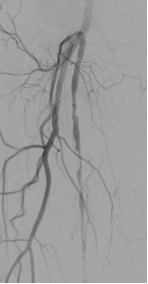

图:造影及通过病变

图:IVUS确认

图:Jetstream 应用

图:DCB 5-250 扩张及全程造影